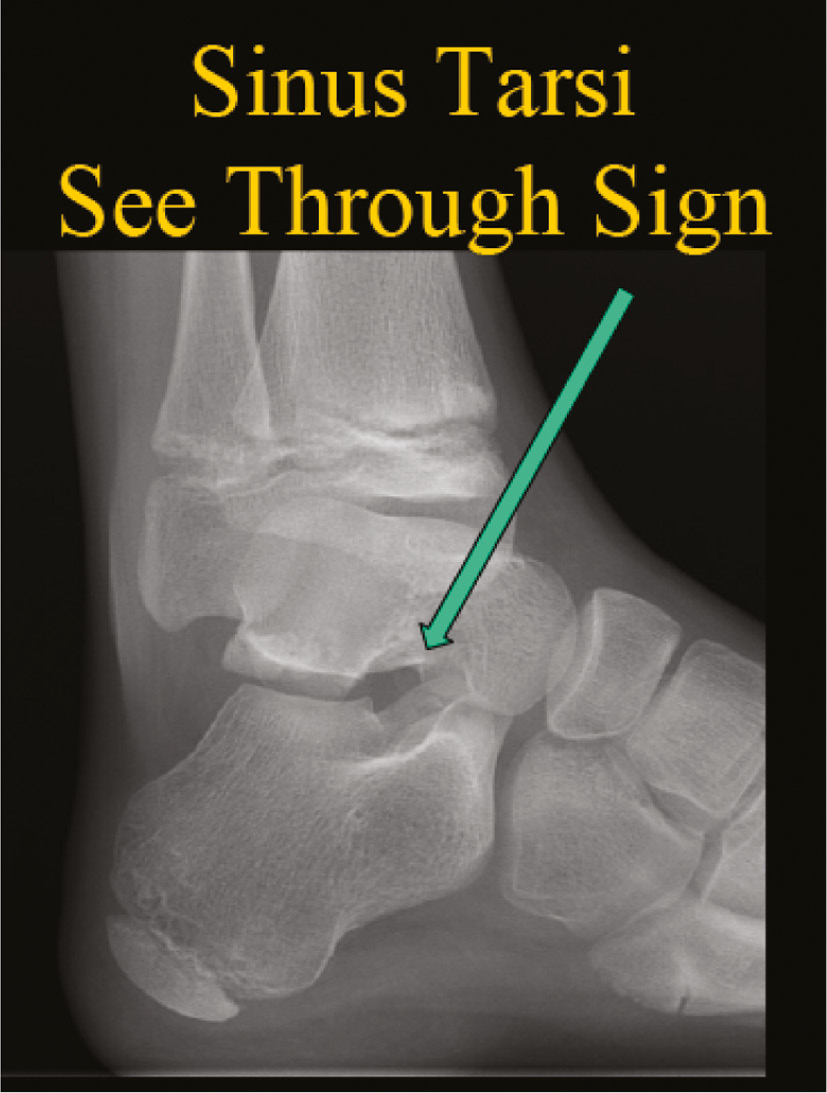

Other findings on the lateral may include the sinus tarsi “see-through” sign (Figure 12) and “double talar dome” sign, a bell-shaped cuboid and increased distance between the base of the 5th metatarsal and medial cuneiform. The oblique radiograph may be useful for the diagnosis of metatarsal stress fractures (Figure 5) or calcaneonavicular coalitions.

Figure 12. Another radiographic characteristic for hind foot varus is the “see-through sign.”

jposna20220035_fig12.jpg